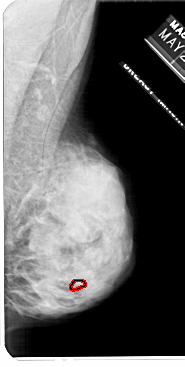

A_1113_1.RIGHT_MLO

LEFT_MLO LINES 4606 PIXELS_PER_LINE 2956 BITS_PER_PIXEL 12 RESOLUTION 43.5 NON_OVERLAY

FILE: A_1113_1.RIGHT_MLO.OVERLAY

TOTAL_ABNORMALITIES 1

ABNORMALITY 1

LESION_TYPE CALCIFICATION TYPE PLEOMORPHIC DISTRIBUTION CLUSTERED

ASSESSMENT 4

SUBTLETY 3

PATHOLOGY MALIGNANT

TOTAL_OUTLINES 1

BOUNDARY